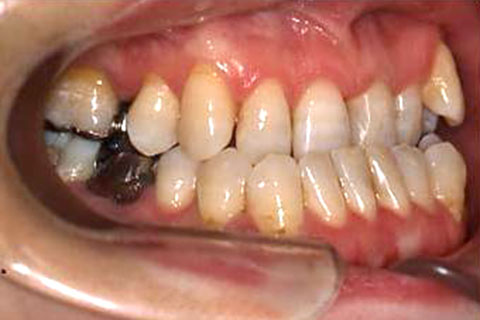

受け口(反対咬合)の症状

下あごが上あごより突出しているか、上あごが下あごより後退している状態で、咬み合わせが逆になっているので反対咬合ともいいます。お子様の場合、受け口(反対咬合)を放置していると、成長期において下あごが過大に成長し悪化しますので、出来る限り早い時期に治療することをおすすめします。受け口(反対咬合)は見た目の問題だけでなく顎の動きを制限し、将来的に顎の痛み(顎関節症)を引き起こす場合があります。また、お子様の場合は、正常な上顎の成長を阻害する可能性があります。

受け口(反対咬合)の症例